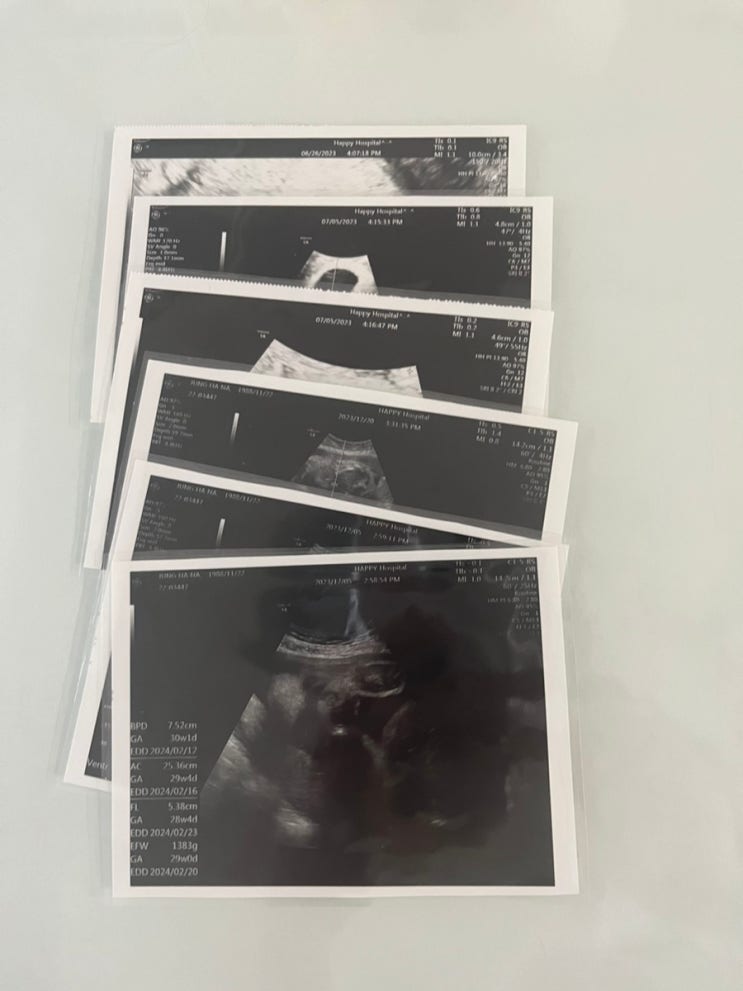

나블하❤️ 안녕하세요 깜나나입니다. 오늘은 다이소에서 셀프 코팅지를 구매 후 초음파 사진을 꾸며볼예정...

[일상] 임신말기 (31주~34주) 초음파검사/산후조리원예약

나블하❤️ 안녕하세요 깜나나입니다. 오늘은 삼팔이 보러가는날 입니다. 행복한병원 지하주차장에 주차를 ...